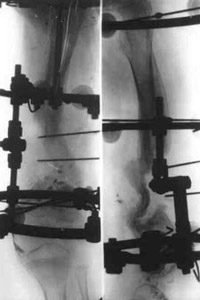

Treatment by means of Ilizarov's apparatus.Treatment by means of Ilizarov's apparatus.Treatment by means of Ilizarov's apparatus.

Treatment by means of Ilizarov's apparatus.

Patient in Ilizarov's apparatus.